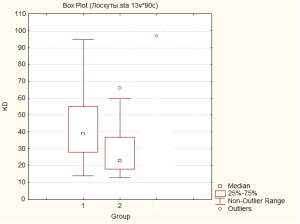

Так, середня тривалість перебування хворих на стаціонарному лікування при проведені пластики дефектів нижньої кінцівки локальними перфорантними лоскутами на живлячий ніжці що включала єдину домінантну перфорантну артерію в групі 1, склала 39,41 ліжко днів з 95% ДІ [[31;54]] (діапазон, 14-95). Даний показник в групі 2, із модифікованим передопераційним обстеженням, що передбачало застосування контрастної КТ-ангіографії для візуалізації перфорантних судин плануємої ділянки клаптя, склав – 23 ліжко-днів з 95% ДІ [[18;36]] (діапазон, 13-66), що свідчить про статистично значуще (p=0,025) скорочення термінів перебування хворих даної групи на стаціонарному лікуванні на 41% (Мал. 7).

Мал..7. Тривалість перебування хворих на стаціонарному лікуванні в досліджуваних групах: група 1 – зі стандартним передопераційним обстеженням; група 2 – із модифікованим передопераційним обстеженням.